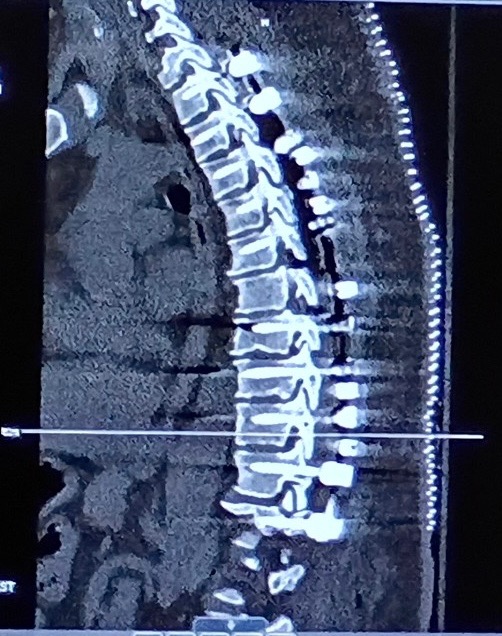

What started off as sciatica pain 3 months ago in my right leg, then my left, then up my abdomen and back with incontinence and being turned away at every turn quickly turned into a dire emergency. I had symptoms of sciatica and doctors told me theirs no cure you’ll just have to live with it. I finally got the help I needed, don’t even ask it was a nightmare. At first even the Neurosurgeon on-call thought it might be Cauda Equina Syndrome because of the classic symptoms, of which I had. After a Lumbar Spinal MRI they quickly ruled that out. Since all my symptoms were showing higher on my abdomen and back the Neurosurgeon on-call requested a Thoracic Spinal MRI that confirmed it was definitely not Cauda Equina Syndrome; which is a herniated/slipped disc that’s narrowing at the end of the spinal canal,; but Thoracic Myelopathy; which is compression of the spinal cord of which mimics the signs and symptoms of Cauda Equina Syndrome, so you could see how that could be presumed as the cause. But the worst of it all they found an extremely Rare Condition called (OPLL); which causes abnormal calcification boney growths throughout the body in random places. In my case the calcified boney growths were growing along my entire thoracic region of my spinal cord. The Surgery - neurosurgeons removed all the calcification from my spinal cord sack and because the calcification was so attached to the spinal cord sack it caused some spinal fluid leakage when they removed it. The Procedure - neurosurgeons removed all my T3-T12 thoracic vertebrae and replaced with 1 rod and 10 screws on each side holding it in place. 2 rods and 20 screws total. Leaving me paralyzed from the sternum down from the Thoracic Spinal Cord Surgery.